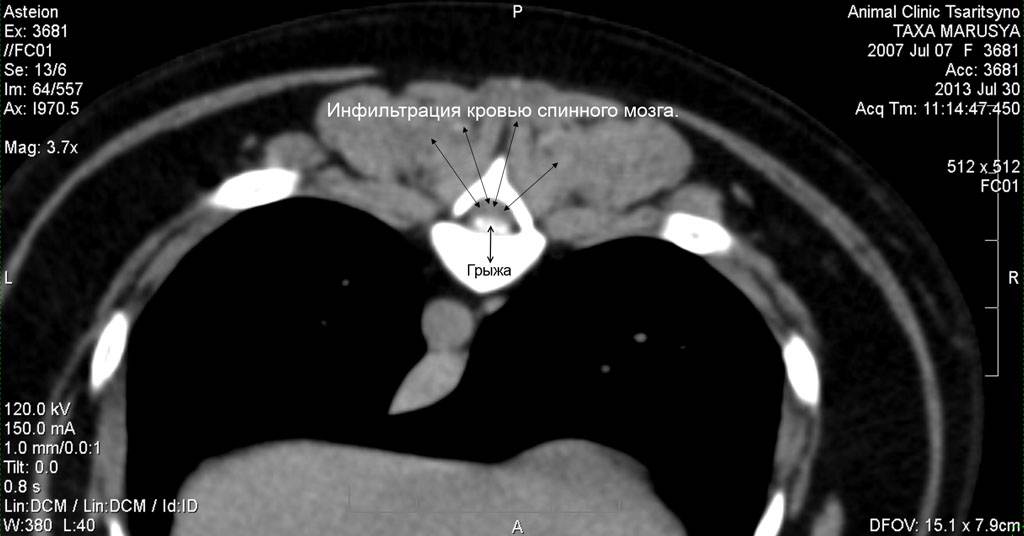

Рис. 1. КТ изображение в мягкотканном окне. Собака породы такса, самка, возраст 6 лет. Грыжа (выпадение) диска между 9 и 10 грудными позвонками. На фото в сагиттальной (серединной) проекции мы видим наличие массы белого цвета в просвете СМ (спинномозгового) канала. Это и есть грыжа диска. Данная грыжа является секвестрированной, т.е. элементы диска, смешавшись с кровью, вывалились в просвет СМ канала и мигрировали краниально (к голове) по СМ каналу. Анамнез болезни: вечером у собаки начали заплетаться задние конечности (парез), вялость, а утром собака не смогла встать (3 степень неврологического дефицита), недержание мочи. При клиническом осмотре выявлен неврологический дефицит 4 степени, т.е. у собаки отсутствовала поверхностная болевая чувствительность

Рис. 2. КТ изображение в мягкотканом окне. Эта же собака. Аксиальная (поперечная) проекция. В просвете СМ канала видна грыжа, которая сдавливает спинной мозг, вызывая нарушение его функции. Данное животное после обследования успешно прооперировано. Реабилитация прошла успешно. Функции задних конечностей восстановились полностью